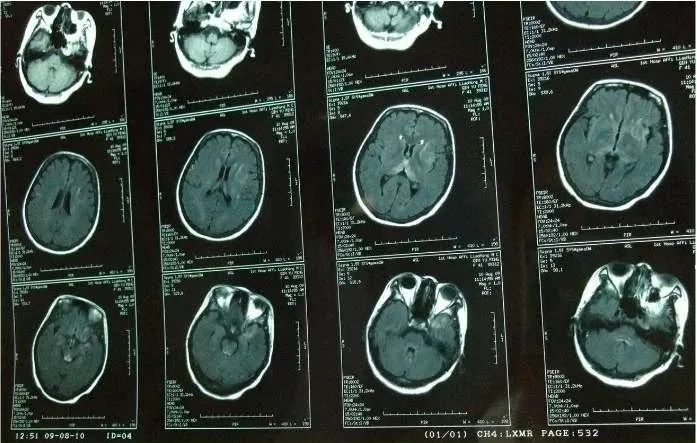

又一个心肺复苏后病人,如何解读